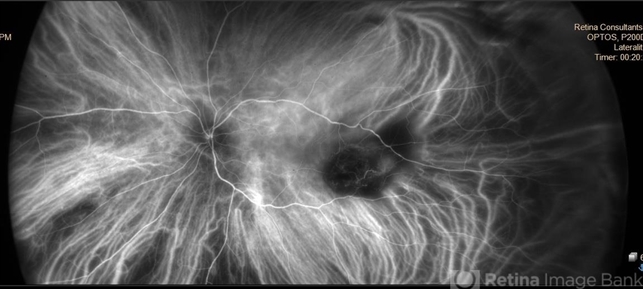

- granulomatous choroiditis, focal chorioretinitis, choroidal neovascular membrane (CNVM), choroidal neovascularization (CNV), fungal endophthalmitis, exudative detachment

- Multimodal imaging of a transplant patient with disseminated Aspergillosis and vision loss in her left eye.